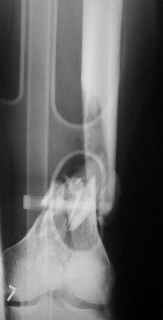

Отправитель: Alexander Chelnokov 31 Октябрь 2004, 20:44

Look what we would have done.